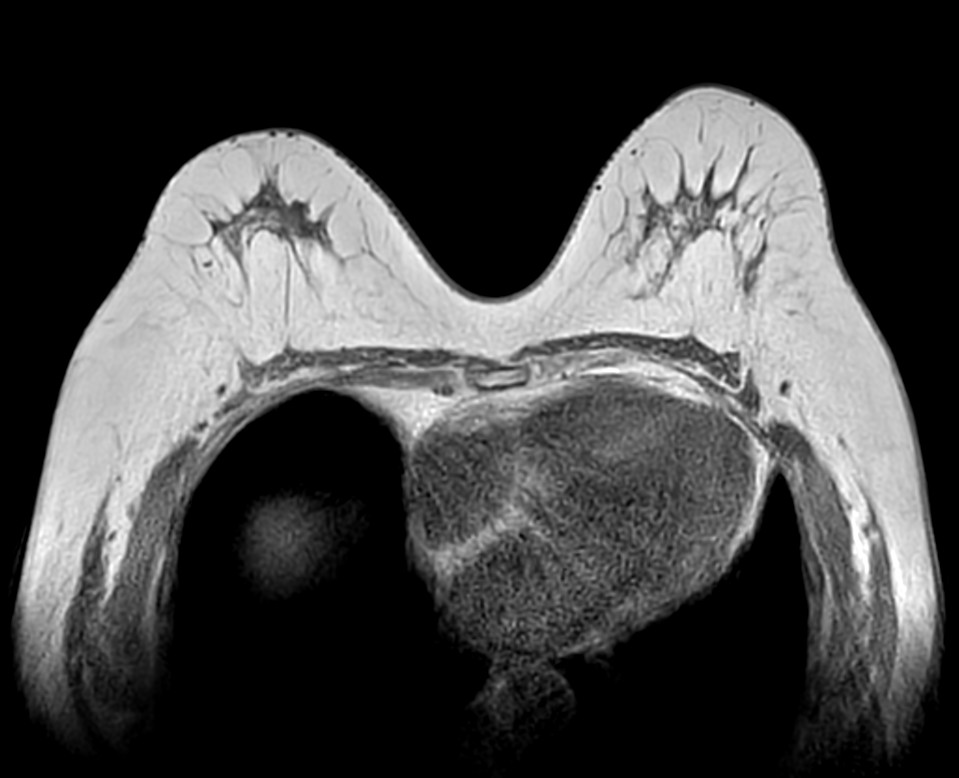

Axial T2w TSE